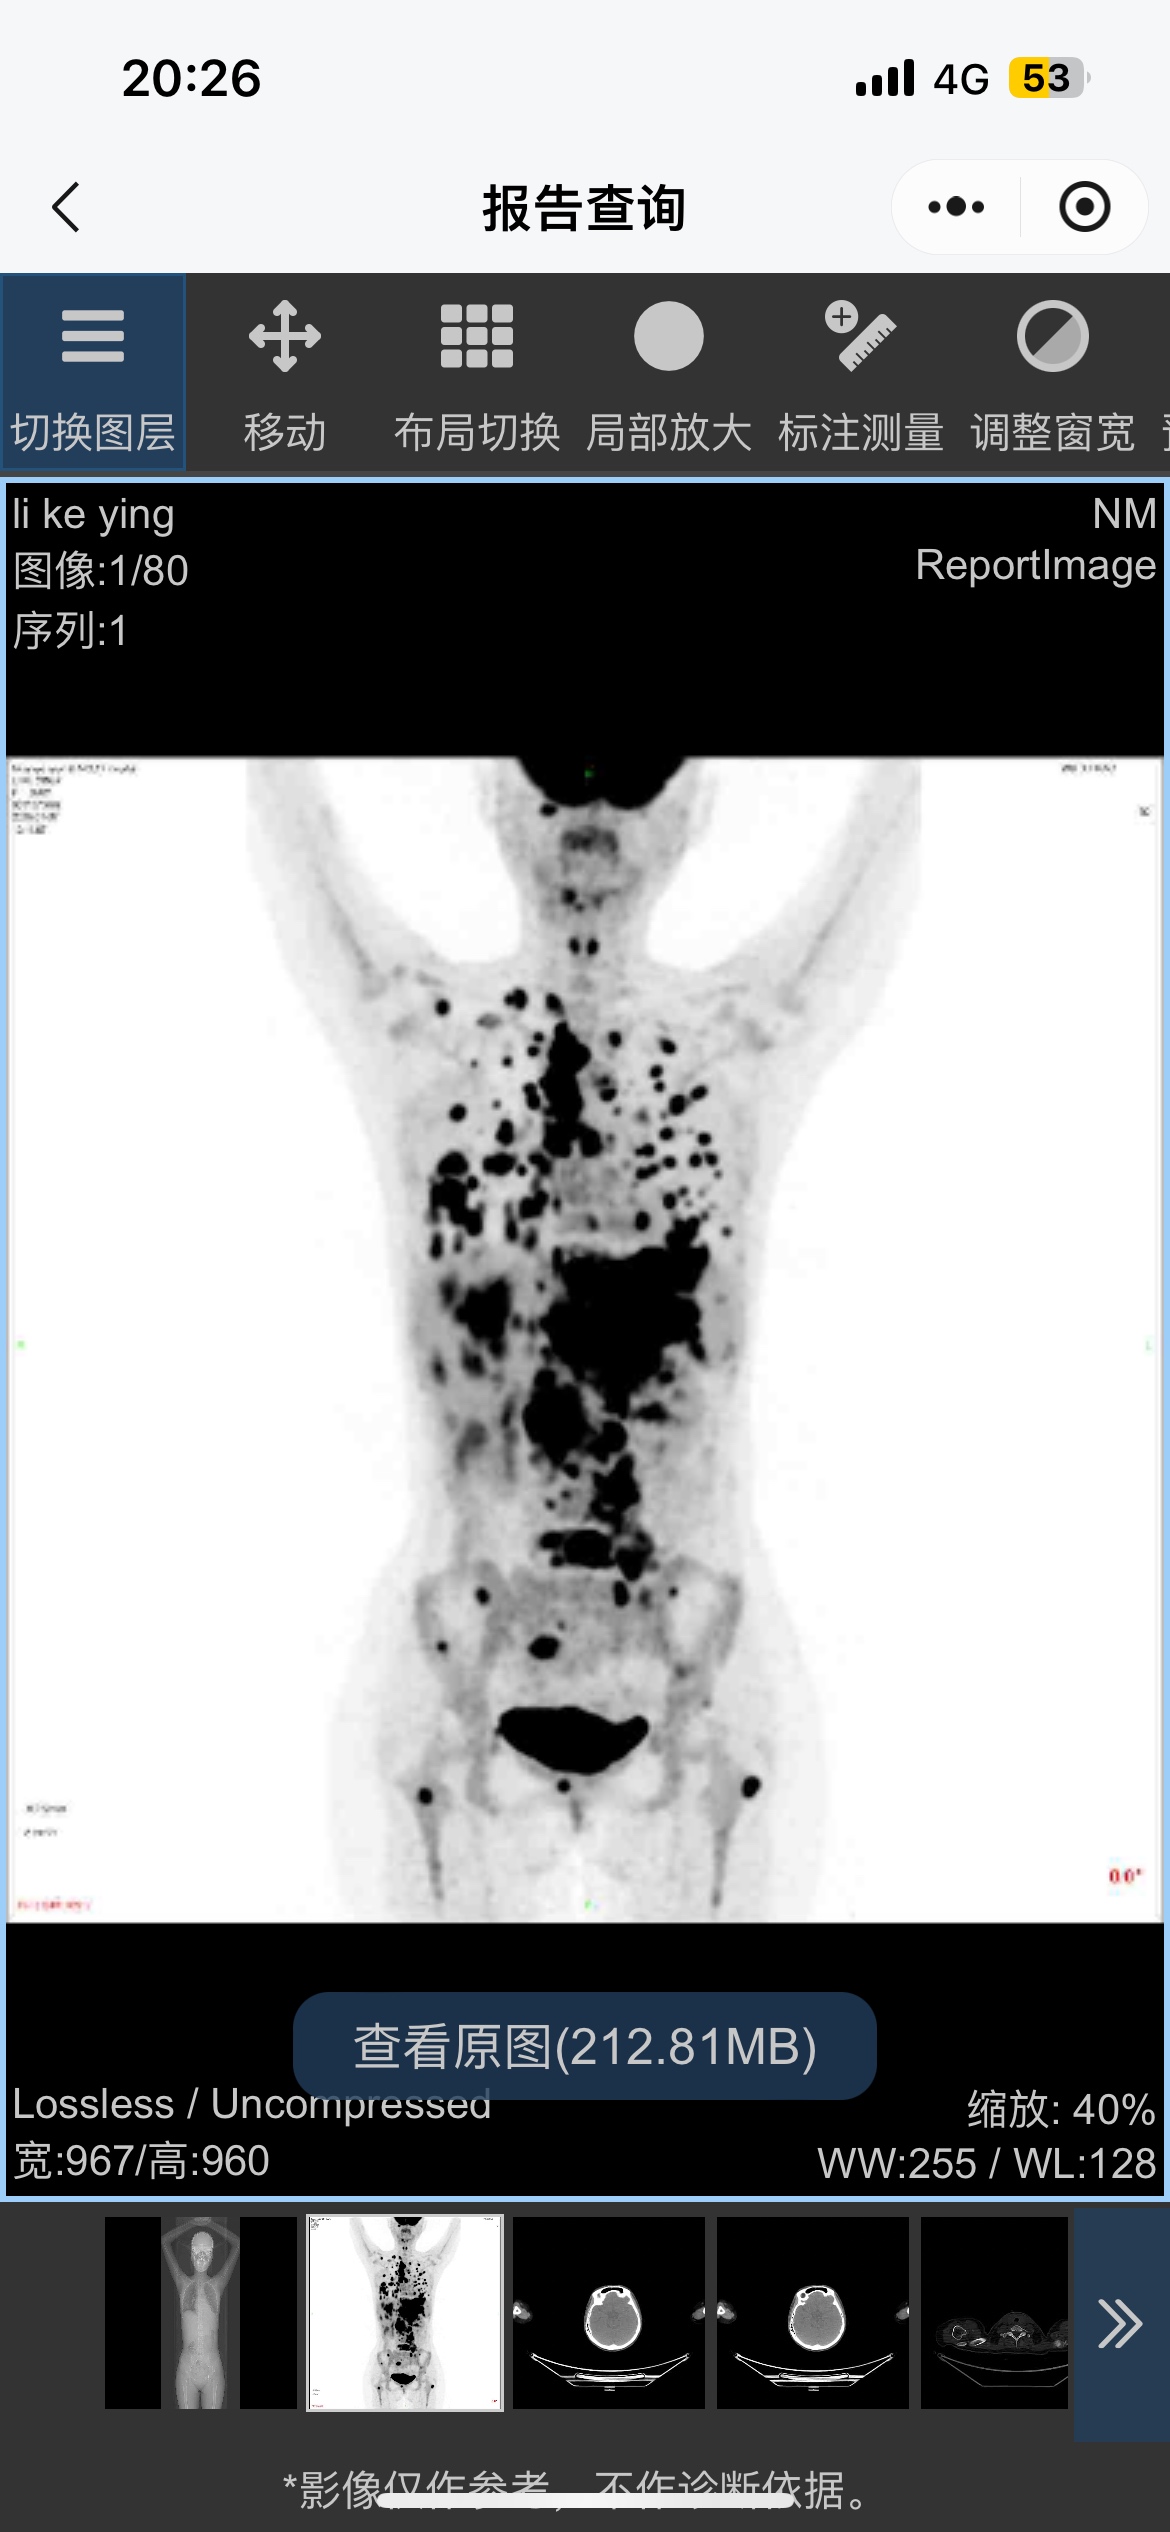

复杂型淋巴瘤求助

两份病理不一样,一份偏向经典霍奇金,一份说是灰区淋巴瘤,免疫组化上看哪份病理更准确?是否还需要送第三份病理进行会诊?

结合年龄和PET CT来判断。原则上说,经典霍奇金极少累及肝脏,当肝脏有累及的时候,要么脾脏一定受累,如果没有,那么应该当作非霍奇金淋巴瘤(大B)来治疗。

大神推荐使用哪个方案呢?

年龄,PET

DA-EPOCH-R+鞘注

大,但是灰区淋巴瘤是比经典霍奇金和原发纵膈大B的预后都差的类型,必须用最强的方案,何况还累及多个结外器官,包括肾脏,肝脏这样的重要器官,治疗不足会很要命。